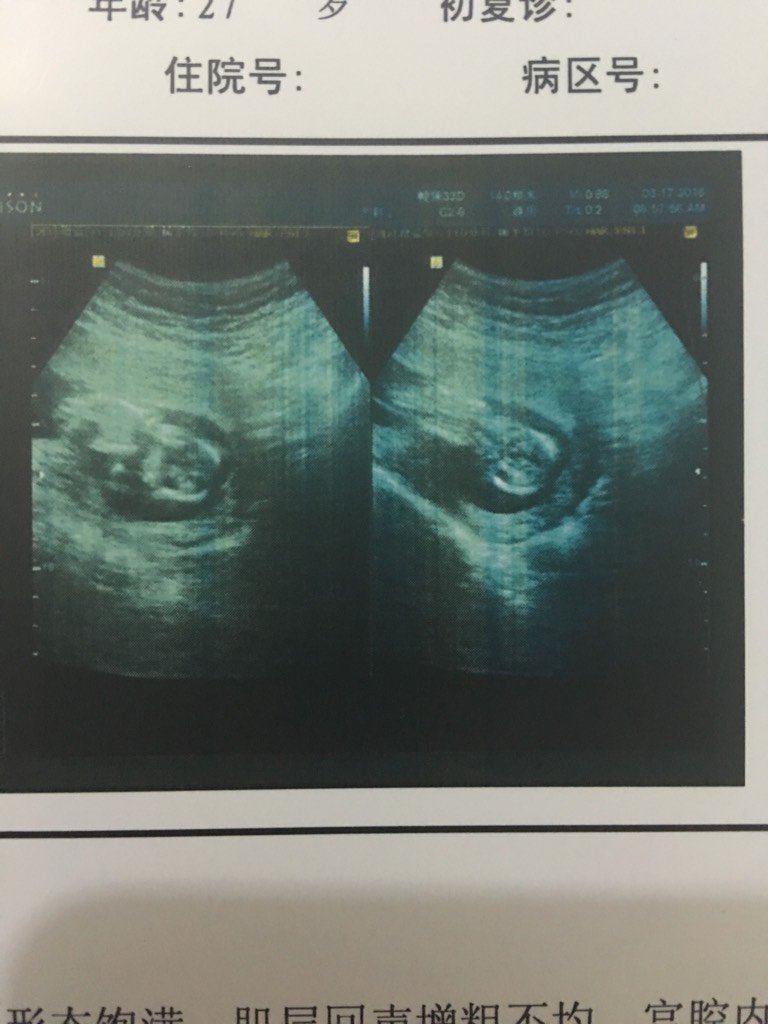

13周加1天的超生医学影像报告单,我想知道孩子脸朝里朝外? 13周加1天的超生医学影像报告单,我想知道孩子脸朝里朝外? 点击展开 樱桃大丸子。 2016-03-19 23:49 为您推荐: 其他回答 胎心140是正常的。 红葡萄石榴 2016-03-20 18:33 好吧 我是看第二张凭自己感觉看的 迎接小天使 2016-03-20 08:50 看不清的,, 爱宝贝果果 2016-03-20 00:08 看不清楚的 wywh 2016-03-20 00:08 看着怎么像潮里面呢 木头家的默默 2016-03-20 00:06 加载更多 相关问题 超声医学影像报告单 超生所见于母体耻骨联合上见胎头双顶径90mm,股骨长径70mm,胎儿脊椎骨排 超生医学影像报告单:子宫轮廓清晰包膜光滑,体 超生医学影像报告单:子宫轮廓清晰包膜光滑,体